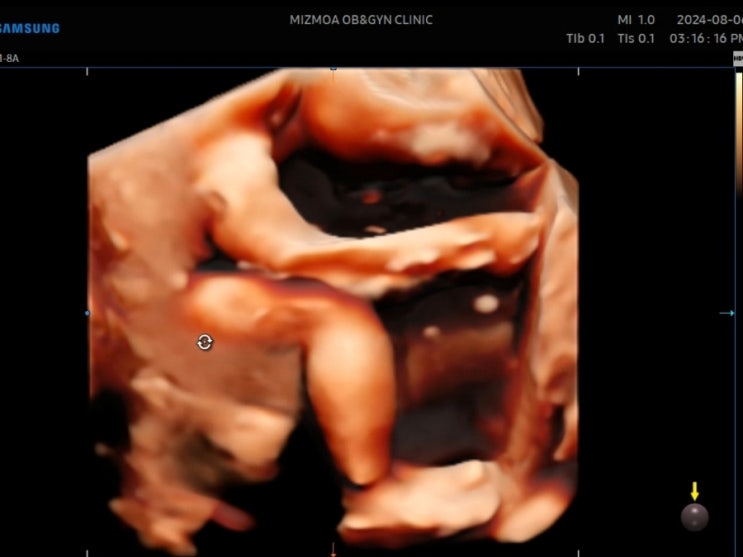

[임신25주~29주] 임당검사 시간 늦음 ㅠㅠ 초음파 태아크기

[임신 22주] 2차 정밀초음파 시기 비용 소요시간

밀린 임신일기 쓰는중.. 아직 출산전이니까! 기록차원에서 호다닥 남겨봅니다.. 양산 미즈모아 산부인과에 ...